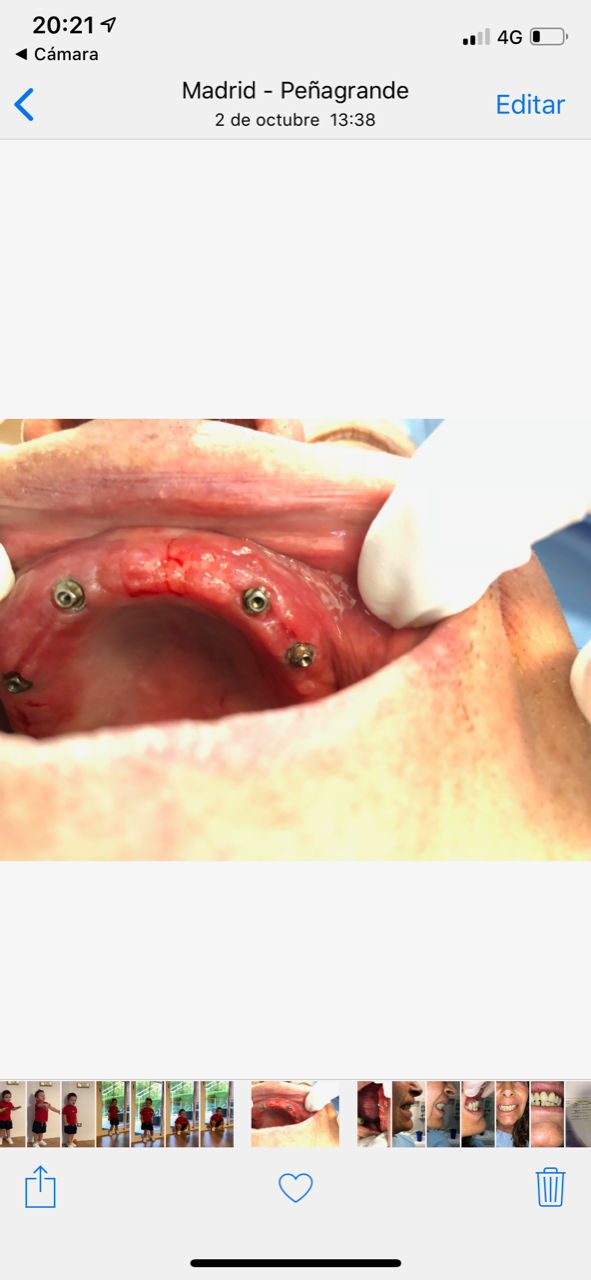

Paciente com reabilitação total inferior com 6 implantes. qual marca?

Conexión externa. Necesitamls saber el tornillo, es de rosca mas estrecha que phibo y 3i.